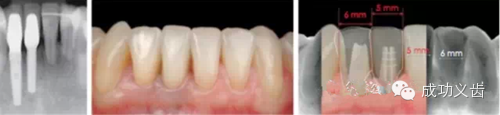

图7.众所周知,相连2颗下前牙的种植修复,考验医师的美学种植控制功力。

图8.相邻2颗下前牙,凸显美学种植控制功力,术后及模式图。在2015年4月3-5日的课程中,Dr.Gamborena将和大家分享他处理这类病例的技巧。绝对干货哦!